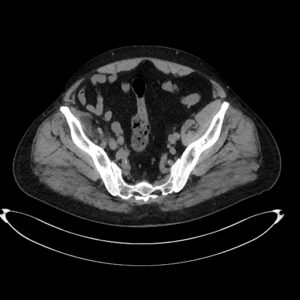

CAZ nr 119: Imagistica CT și IRM la un pacient cu tumoră stromală gastro-intestinală (GIST)

Video 1: reconstrucție axială din achiziție CT 4 faze: nativ, arterial, venos și tardiv

Discuţie caz nr 119: pacientul efectuează CT în vederea operației pentru defect de perete abdominal anterior și se evidențiază o leziune expansivă în spațiul gastro-hepatic care este hipodensă nativ comparativ cu parenchimul hepatic și care este izodensă cu parenchimul hepatic în tip arterial, venos și tardiv. Pacientul este trimis la IRM pentru caracterizare tisulară suplimentară și se remarcă că leziunea este în hipersemnal T2, hiposemnal T1 comparativ cu parenchimul hepatic, prezintă priză de contrast, este în contact cu faţa viscerală a lobului stâng hepatic și se continuă cu peretele gastric la nivelul antrului – suspiciunea este de GIST.